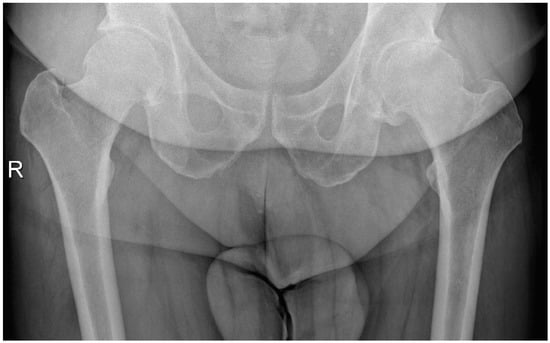

Acetabular reaming and cup placement were performed using offset reamers and cup insertion handles. After a capsular release performed with electrocautery, the femur was prepared using a single custom-made rasp. The custom-made femoral stem, with 2/3 hydroxyapatite coverage and ceramic femoral heads, was implanted, and hip stability was checked post-reduction. Figure 4 and Figure 5 show a patient with coxarthritis of the left hip and his postoperative X-ray.

Figure 4. Male patient (53 years old) with coxarthritis of the left hip.